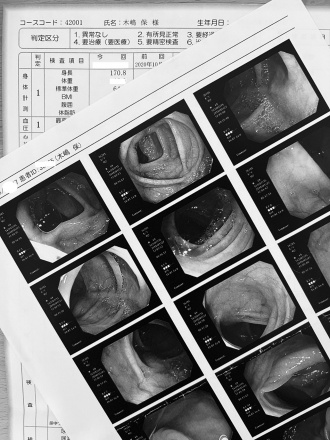

今回は大腸カメラ検査も行いましたが、検査前は結構ドキドキでした。

大きな問題もなく、また1年頑張れそうです。